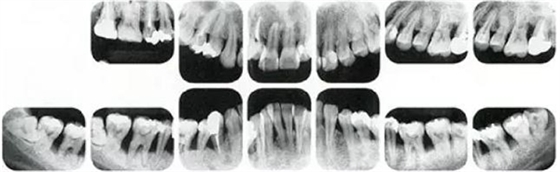

右邊參考病例

①的患者是35歲女性。4~10mm的牙周袋和大量的牙石。特別是在左上、右下、左下的磨牙處能看到大量牙槽骨吸收。這名患者是慢性牙周炎,僅在磨牙處有局部由風(fēng)險(xiǎn)因子導(dǎo)致(解剖學(xué)形態(tài))導(dǎo)致的重度病癥發(fā)展。

另一方面25歲女性的參考病例

②將會(huì)是什么樣的呢?左上、右下、左下的磨牙處有大量牙槽骨吸收,考慮到其發(fā)病年齡,斷定為是侵襲性牙周炎局部型。

但是實(shí)際上參考病例①和②是同名患者,①是②10年后的狀態(tài)。這名患者間隔10年后來就診,讓我們可以確認(rèn)到癥狀的變化。

在日常臨床中,還毫無自覺中病情發(fā)展的患者很多,如果不知道患者年齡=很難下診斷是頻繁的。

●參考病例① 35歲女性

35歲女性。妊娠4個(gè)月。過去雖然接受過刷牙指導(dǎo),但菌斑控制狀態(tài)依然不理想?;颊哂邪l(fā)現(xiàn)自己刷牙時(shí)牙齦出血。

●參考病例② 25歲女性

25歲女性。菌斑控制狀態(tài)不好。齦溝除磨牙處外全在3mm以下,X光照片上左上、右下、左下的第一磨牙上有垂直性骨吸收。這個(gè)病例是參考病例①10年前的狀態(tài),是典型的侵襲性牙周炎局部型。